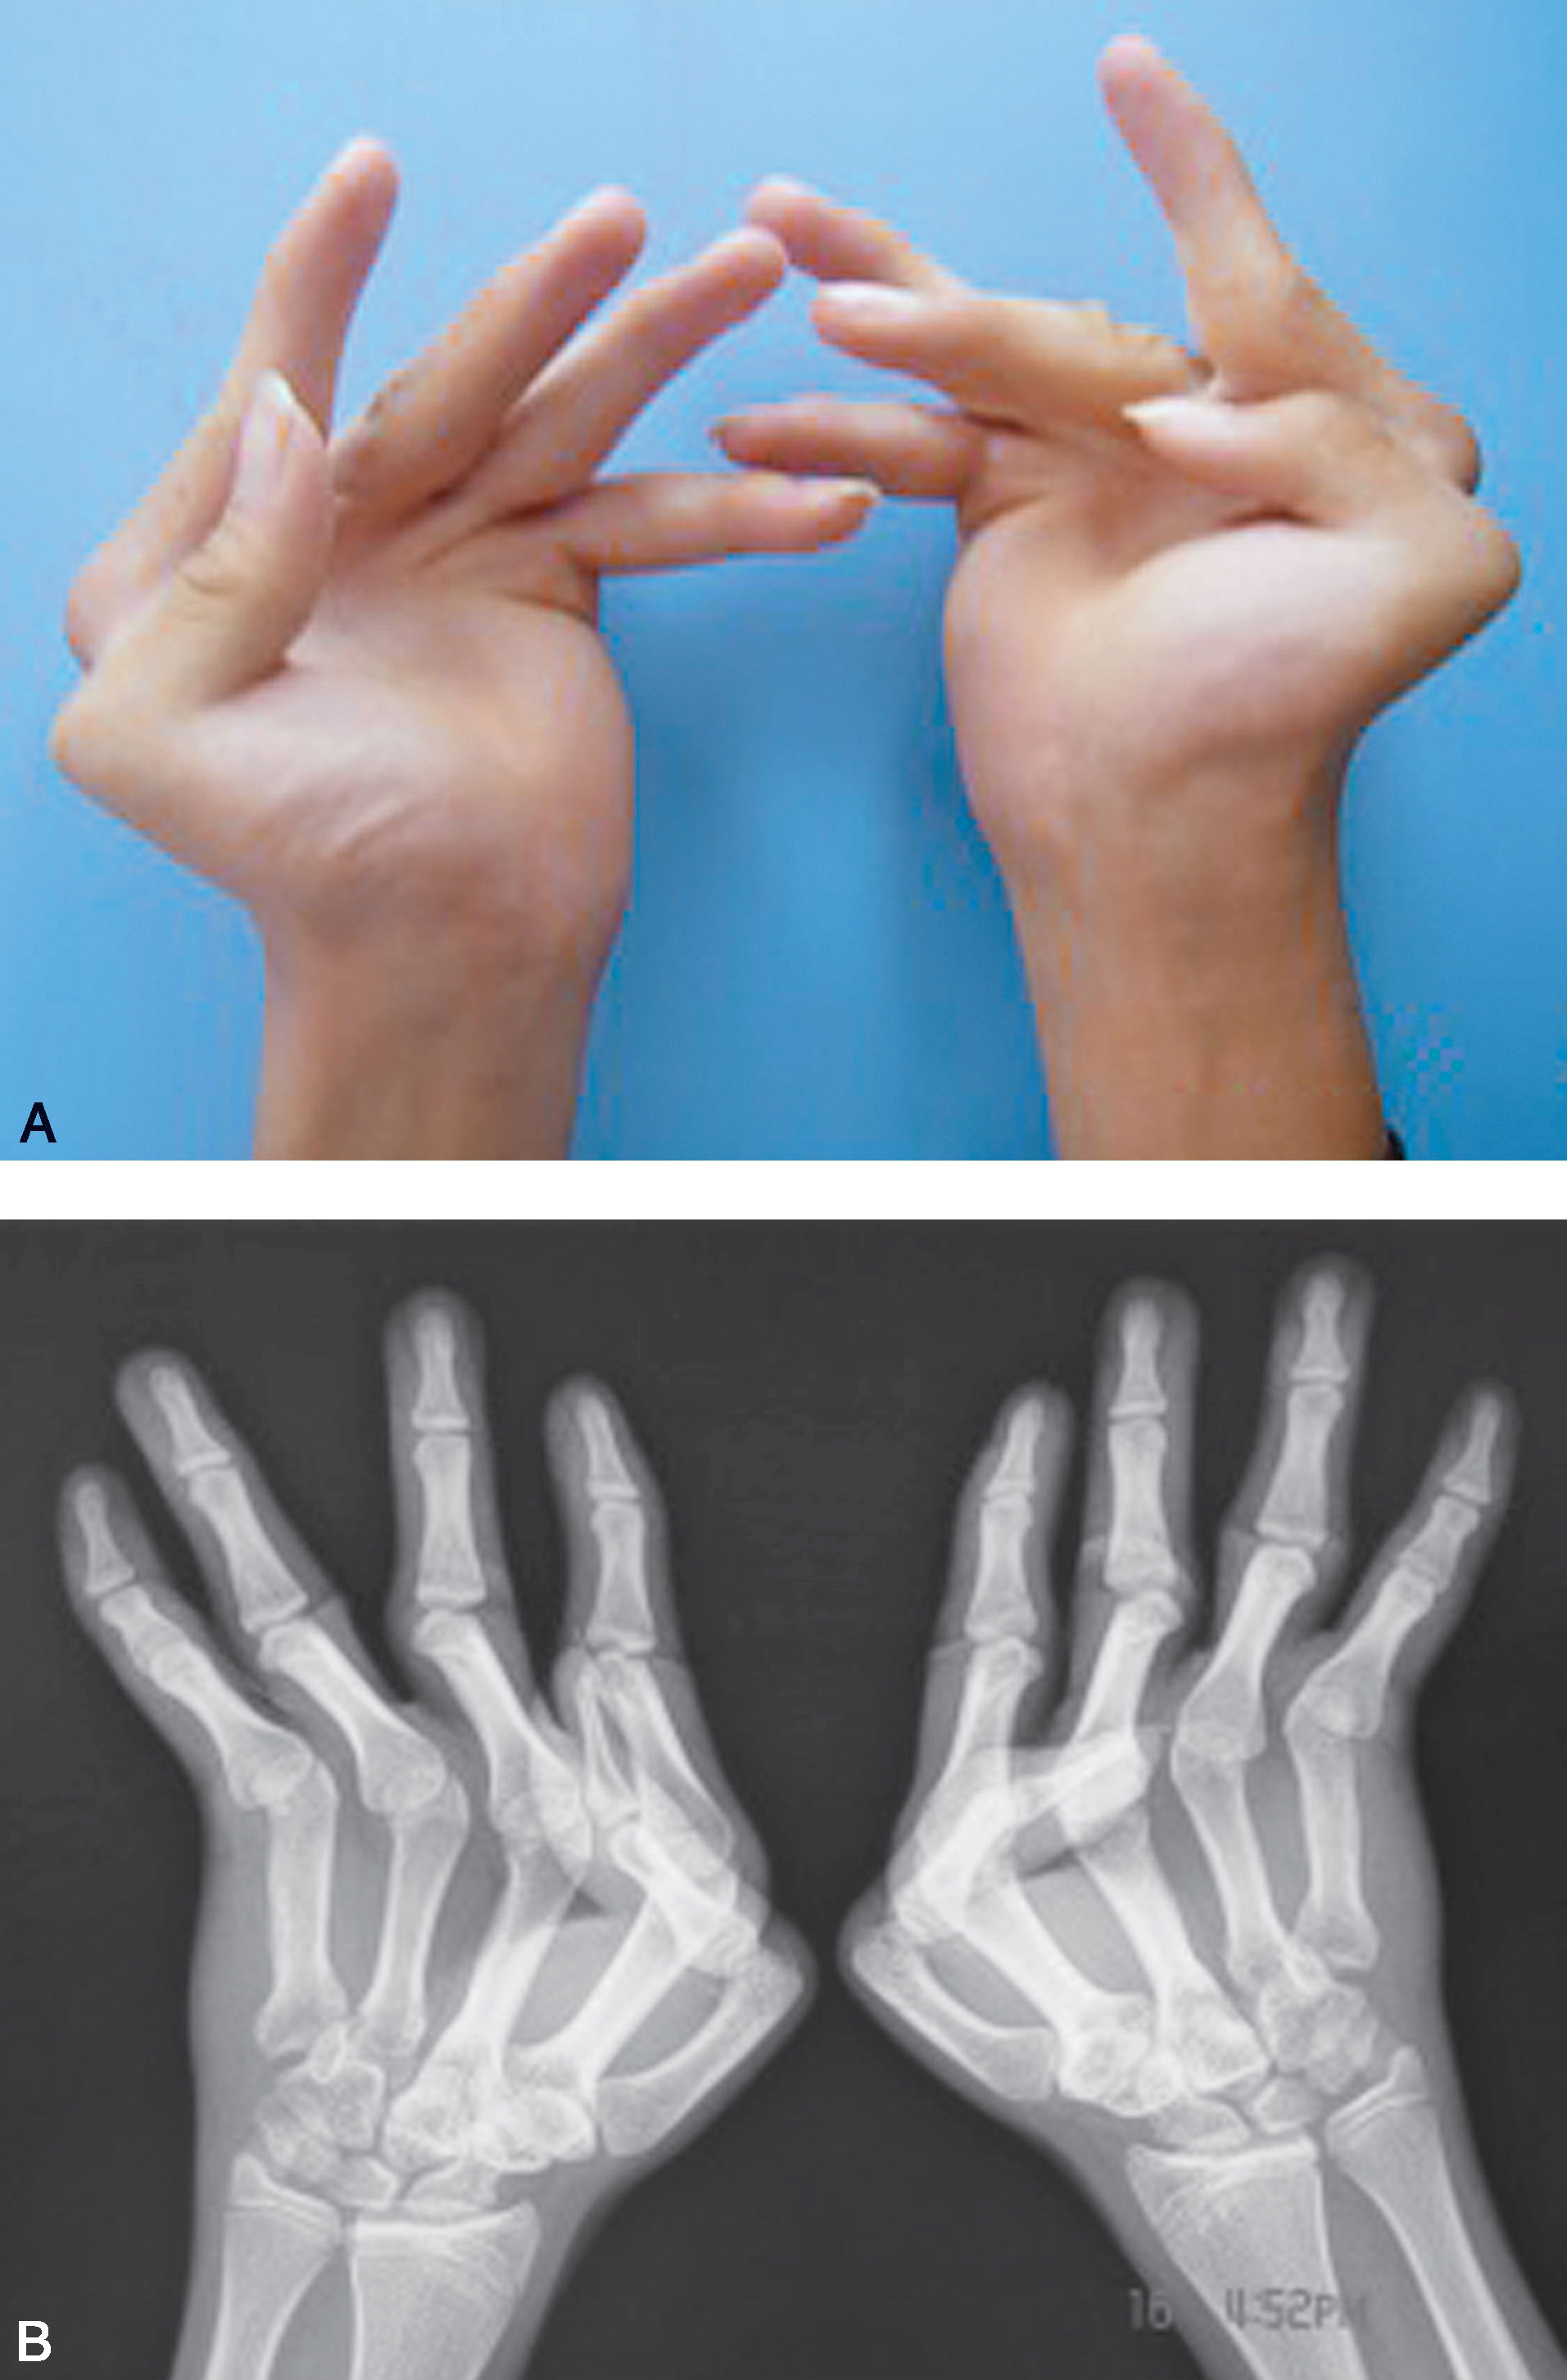

A.先天性吹风手畸形(双侧)掌指关节屈曲挛缩、尺偏;B.X 线片显示掌指关节屈曲、尺偏明显

图1-2-18 关节屈曲畸形病例